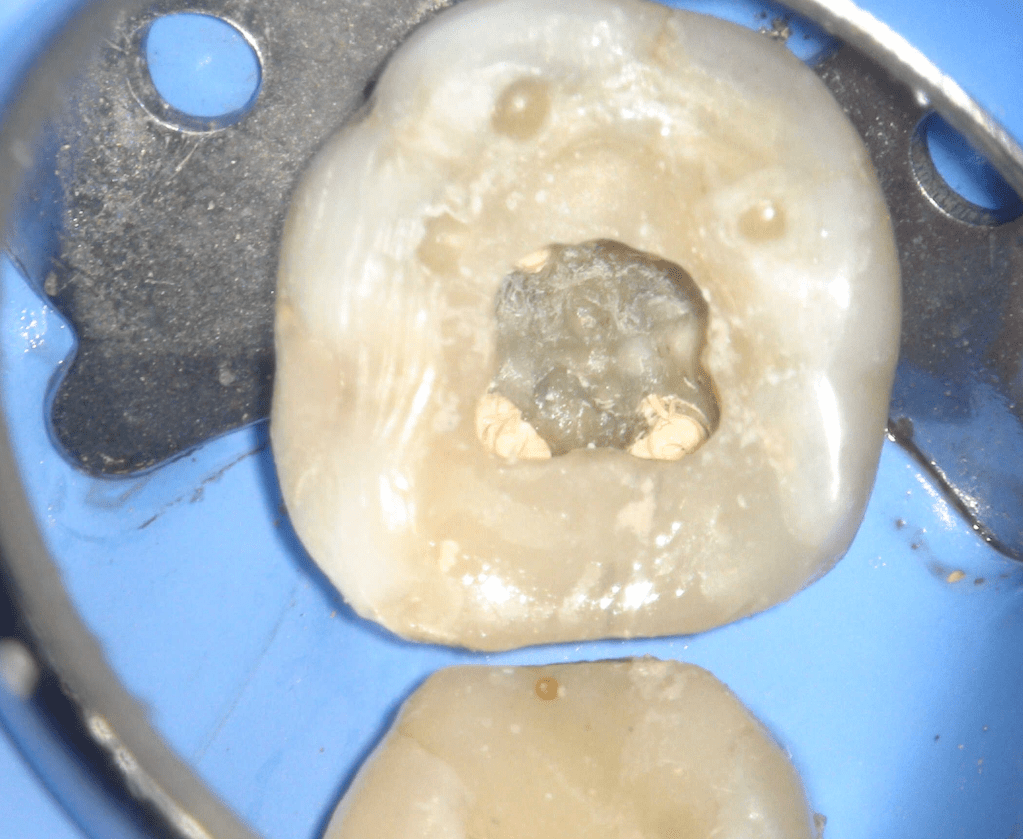

Pulpotomía biodentine + reco preendio